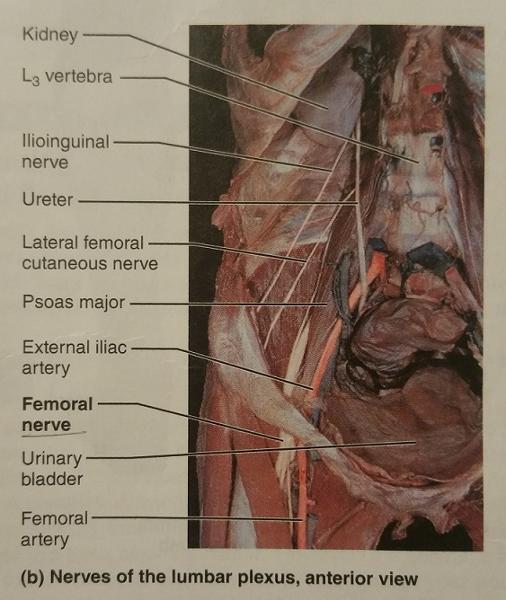

The lumbar plexus arises from the ventral rami of what lumbar nerves (and sometimes which thoracic nerve)?

L1-L4 and sometimes T12

The nerves of the lumbar plexus serves which region and which body part?

Serves the lower abdominopelvic region and the anterior thigh

What is the largest nerve of the lumbar plexus?

Femoral nerve

The femoral nerve arises from the ventral rami of what lumbar nerves?

L2-L4

The femoral nerve innervates which group of muscles? (Give an example)

Anterior thigh muscles

Ex. Sartorius muscle

The cutaneous branch of the femoral nerve also serves what general feature of which general body part?

Supply the skin of the anteromedial surface of the entire lower limb

Identify the blanks.

Identify the blanks.

Identify the blanks.

Identify the blanks.

Identify the blanks.

Identify the blanks.

Identify the blanks.

Identify the blanks.

Identify the blanks.

Identify the blanks.